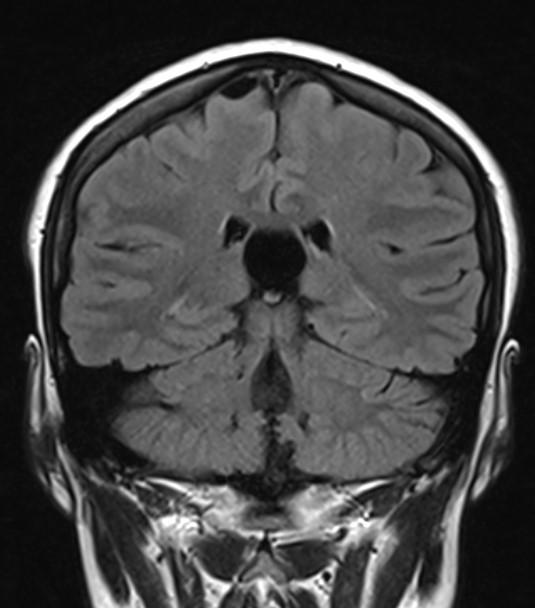

MR images incidentally revealed a triangular-shaped CSF space between the lateral ventricles (arrows).

Axial MR/CT image shows a triangular-shaped CSF space situated behind the foramen of Monro, between the lateral ventricles. Coronal image demonstrates the elevated and splayed fornices.